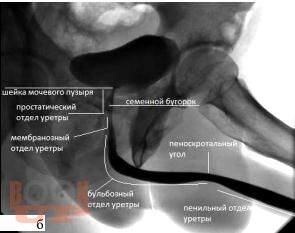

Стриктурная болезнь уретры

В учебном пособии рассматриваются вопросы, посвященные этиологии, патогенезу и современным методам диагностики стриктурной болезни уретры, а также содержится информация о выборе тактики и способах лечения данной патологии.